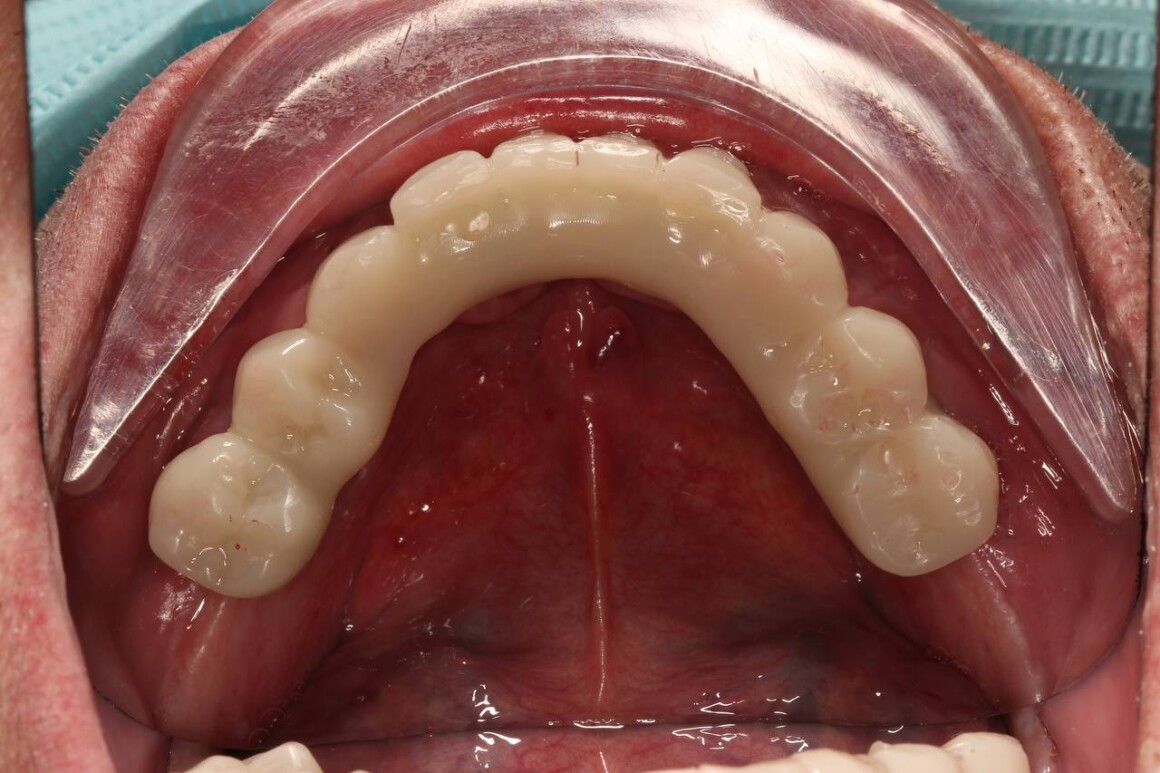

Постоянный протез ALL on 6 на верхней челюсти

Адаптационные протезы ALL on 4